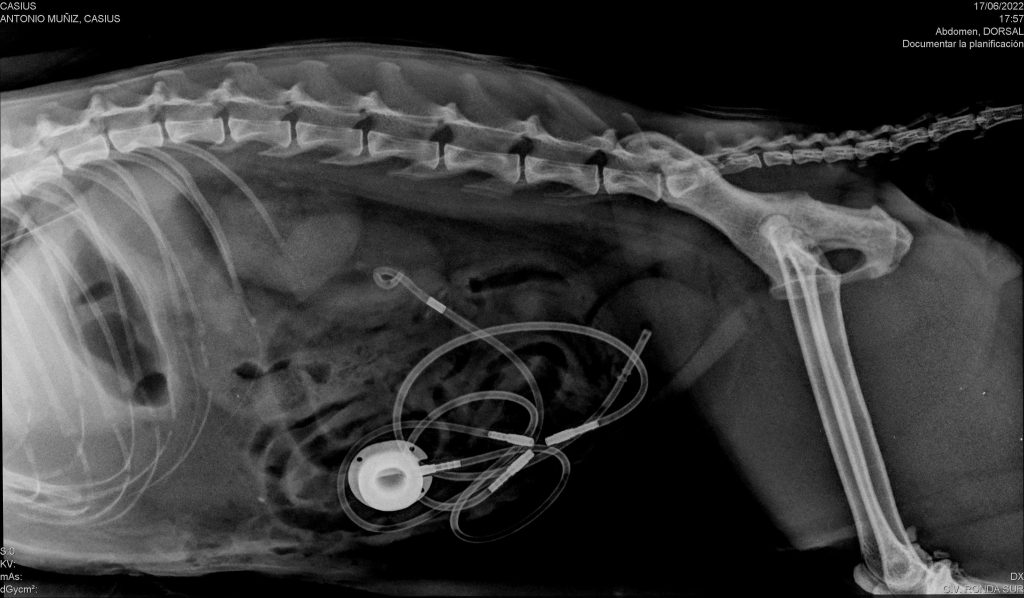

-Urinario: (Colocación de stents ureterales en obstrucciones…

-Colocación stent ureteral en obstrucciones (foto)